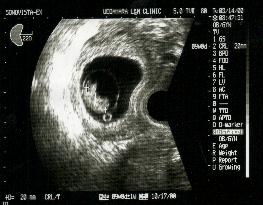

妊娠8週〜9週

胎児は頭、胴体、手、足が見え始めます。小さいけれども子宮の中で元気に泳いでいます。

胎児が20mm〜30mmになったら予定日を決めましょう。

予定日が決まったら母子手帳をもらいましょう。